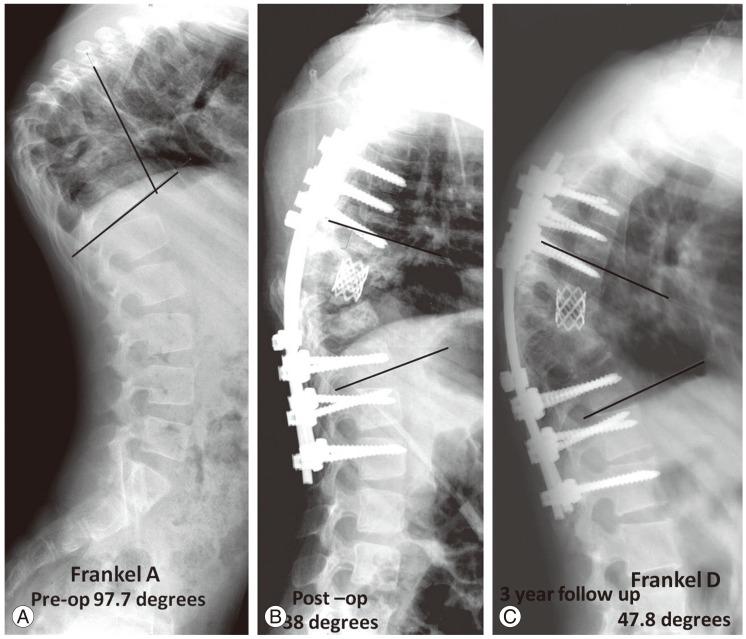

Disease-healing with bony fusion (interbody fusion) was seen in 97.5% of cases. Average deformity (kyphosis) correction was 54.6% in dorsal spine and 207.3% in lumbar spine. Corresponding loss of correction was 3.6 degrees in dorsal spine and 1.9 degrees in the lumbar spine. Neurological recovery in Frankel B and C paraplegia was 85.7% and 62.5%, respectively.

97.5%的病例实现了骨融合(椎间融合)的疾病愈合。胸段脊柱平均畸形(后凸)矫正率为54.6%,腰段脊柱为207.3%。相应的矫正度丢失胸段脊柱为3.6度,腰段脊柱为1.9度。Frankel B级和C级截瘫患者的神经功能恢复率分别为85.7%和62.5%。